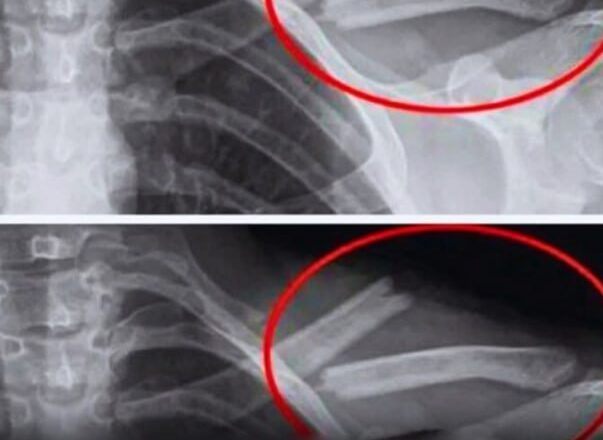

Дослідження показують, що надмірне вживання газованої води призводить до зниження щільності кісток, особливо у жінок. Іншими словами, ваші кістки стають слабшими… іноді без будь-яких симптомів, аж до перелому.

Дослідження, проведене в США за участю 2500 жінок, показало, що ті, хто регулярно пив колу, мали нижчу щільність кісток у стегнах. І вони робили це несвідомо.

Дослідження, проведене серед дівчат-підлітків, також виявило зв’язок між споживанням газованої води та підвищеним ризиком переломів.